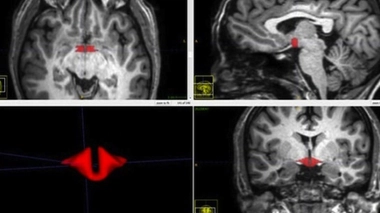

Les femmes sous pilule présentent "une différence spectaculaire" dans leur cerveau